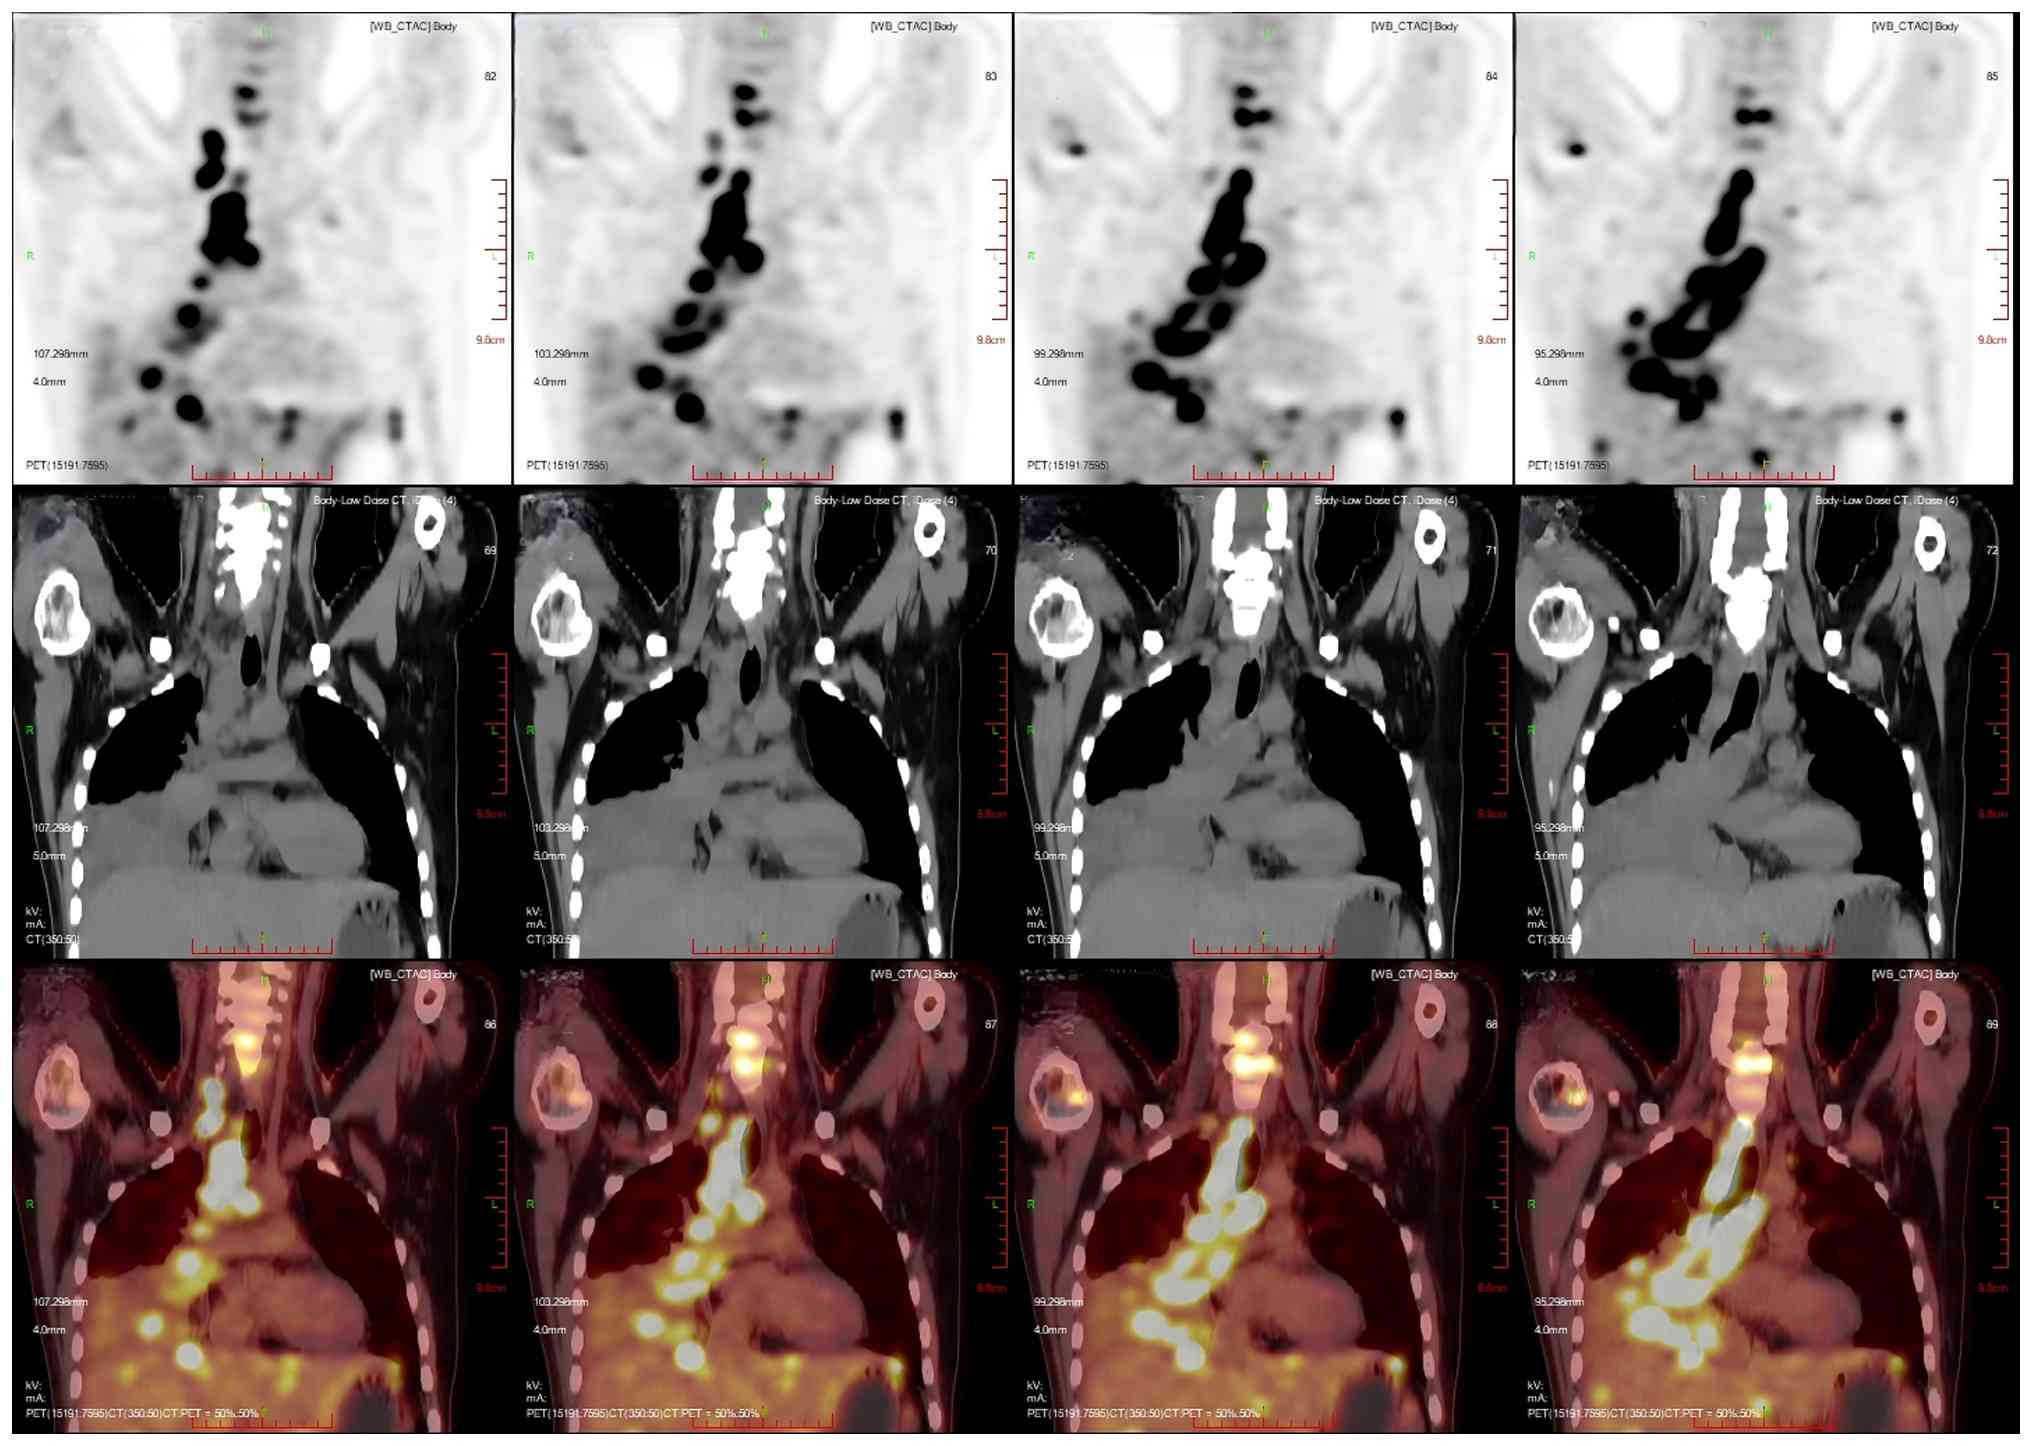

After 1 month, the patient developed numbness and discomfort below the waist, weakness of both lower limbs and limitations to lifting. To clarify the changes in the condition of the patient, positron emission tomography/CT (PET/CT) was performed. PET/CT images showed that an irregular mass-like hyperdense shadow was detected in the right lung hilar and the middle and lower lobes of the right lung; no normal lung tissue was seen, the lesion crossed the interlobular pleura and invaded the upper lobe of the right lung, and the corresponding area on PET showed a mass-like radiolucency focus with an maximum standardized uptake value (SUVmax) of 25.8 (Fig. 5). Multiple enlarged and swollen lymph nodes were detected in the mediastinum, bilateral pulmonary hilar region, bilateral diaphragmatic pedicle and right cardiogenic angle area, partially fused in the form of a mass. PET showed a mass of radiolucent foci in the corresponding areas, and the SUVmax of the hypermetabolic area under the bronchus was measured to be 21.4. Thickening of the right pleura was observed, an arcuate fluid density shadow was seen in the thoracic cavity and mild radiolucent uptake was visible in the area of pleural effusion on the right side of the chest cavity (Fig. 6). The liver was full, with diffuse low-density nodules and masses of varying sizes within it, and PET showed nodular and mass-like radioactivity uptake in the corresponding areas. The low-density mass in the S4 segment of the liver was measured to be ~5.0×4.4 cm in size, with an SUVmax of 20.0. Several enlarged lymph nodes were observed in the portal region of the liver, which had fused to form a mass. PET scans showed mass-like radioactivity uptake in the corresponding areas, with a SUVmax of 20.2 (Fig. 7). Multiple nodular and striated radiographic uptake of the right humeral head, multiple parts of the sternum, bilateral scapulae, cervical, thoracic and lumbar vertebral bodies, part of the accessory bones, the two flanks of the sacrum, multiple parts of the pelvic bone and the proximal segment of the left femur were noted. CT demonstrated an inhomogeneous increase in the density of the bone at the corresponding sites, discontinuity of the cortex in some of the neighboring bones, flattening of the seventh thoracic vertebral body, morphological disorders and an increase in the peripheral soft-tissue shadows. A high metabolic area was measured in the seventh thoracic vertebral body, with an SUVmax of 20.4 (Fig. 8).

Multiplanar 18F-FDG PET/CT imaging of

the patient's chest with diffuse hypermetabolic lymph nodes and

right pleural effusion. Multiple enlarged and swollen lymph nodes

were detected in the mediastinum, bilateral pulmonary hilar region,

bilateral diaphragmatic pedicle and right cardiogenic angle area,

partially fused in the form of a mass. PET showed a mass of

radiolucent foci in the corresponding areas, and the

SUVmax of the hypermetabolic area under the bronchus was

measured to be 21.4. Thickening of the right pleura was observed,

an arcuate fluid density shadow was seen in the thoracic cavity and

mild radiolucent uptake was visible in the area of pleural effusion

on the right side of the chest cavity. Imaging modalities: PET (top

row); CT (middle row); PET/CT fusion imaging (bottom row). Imaging

planes: All panels present coronal plane views, consisting of

serial craniocaudal coronal sections (progressing from right to

left across this panel series). These views illustrate the spatial

distribution of hypermetabolic lymphadenopathy across

mediastinal/hilar compartments, as well as the anatomical

relationship between the nodal lesions and right pleural effusion.

CT, computed tomography; PET, positron emission tomography.

Figure 6.

Multiplanar 18F-FDG PET/CT imaging of the patient's chest with diffuse hypermetabolic lymph nodes and right pleural effusion. Multiple enlarged and swollen lymph nodes were detected in the mediastinum, bilateral pulmonary hilar region, bilateral diaphragmatic pedicle and right cardiogenic angle area, partially fused in the form of a mass. PET showed a mass of radiolucent foci in the corresponding areas, and the SUVmax of the hypermetabolic area under the bronchus was measured to be 21.4. Thickening of the right pleura was observed, an arcuate fluid density shadow was seen in the thoracic cavity and mild radiolucent uptake was visible in the area of pleural effusion on the right side of the chest cavity. Imaging modalities: PET (top row); CT (middle row); PET/CT fusion imaging (bottom row). Imaging planes: All panels present coronal plane views, consisting of serial craniocaudal coronal sections (progressing from right to left across this panel series). These views illustrate the spatial distribution of hypermetabolic lymphadenopathy across mediastinal/hilar compartments, as well as the anatomical relationship between the nodal lesions and right pleural effusion. CT, computed tomography; PET, positron emission tomography.